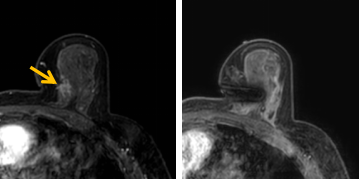

患者李女士磁共振檢查發(fā)現(xiàn)右乳內(nèi)側(cè)高度可疑病變,病變小摸不到,超聲和X線攝影(鉬靶)都看不到,怎么辦?要想明確病變性質(zhì),必須進(jìn)行磁共振引導(dǎo)下精準(zhǔn)足量的活檢,但是這種技術(shù)操作難度大、軟硬件要求高。

經(jīng)過仔細(xì)查體并分析所有影像資料,陳寶瑩發(fā)現(xiàn),病變靠近胸大肌,容易造成術(shù)中損傷。患者乳房較小,病變?cè)趦?nèi)側(cè),導(dǎo)致乳房不易固定,進(jìn)針難度大,與患者充分溝通后,陳寶瑩帶領(lǐng)團(tuán)隊(duì),制定了細(xì)致的操作方案,術(shù)中,醫(yī)護(hù)團(tuán)隊(duì)反復(fù)調(diào)整體位和固定架的角度及方向,利用隔離技術(shù)保護(hù)好周圍組織。受乳房形態(tài)和病變位置的限制,醫(yī)生只能蹲著、跪著進(jìn)行操作,經(jīng)過30多分鐘終于順利完成,精準(zhǔn)獲取了足量的組織,而且一針到位,創(chuàng)傷小、出血少,患者沒有任何不適,做完即回家休息。幾天后,病理證實(shí)是一種特殊類型的早期乳腺癌,為后續(xù)進(jìn)一步治療方案的制訂提供了準(zhǔn)確依據(jù)。